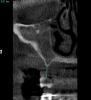

SergeyAL Опубликовано 29 мая, 2013 Поделиться Опубликовано 29 мая, 2013 коллеги столкнулся с такой ситуацией 5 лет назад были установлены поднадкостничные имплантаты имени д-ра Раада пациенту пообещали, что 5 лет они точно прослужат на срезах КТ видно, что прослужили, но в некоторых местах албвеолярного отростка не осталось после их службы)) послу удаления их остались сплошные рубцы, удалять которые смысла не импло, т.к. они были спаяны со Шнайдеровой мембраной или то, что от нее осталось последние фотографии через 4 месяца после их удаления, слизистая представляет собой сплошной рубец. коллеги, поделитесь, какую тактику применяете при выраженных рубцовых деформациях, когда впереди еще костная пластика, имплантация и т.д. Ссылка на комментарий

SergeyAL Опубликовано 30 мая, 2013 Автор Поделиться Опубликовано 30 мая, 2013 коллега, каких синусов, толщина в области синуса менее 3-х мм, а расстояние от костной ткани до предполагаемой реставрации 10-15мм!!!!! Ссылка на комментарий

SergeyAL Опубликовано 30 мая, 2013 Автор Поделиться Опубликовано 30 мая, 2013 там выраженная редукция тканей по ширине,даже в в области синуса около 3 мм Ссылка на комментарий

SergeyAL Опубликовано 30 мая, 2013 Автор Поделиться Опубликовано 30 мая, 2013 там не везде есть костная пластинка, местами рубцы из ротовой полости спаяны со Шнайдеровой мембраной или что там от нее осталось Ссылка на комментарий